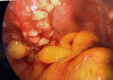

Fig. 2

Nodular Excresences distributed along Pelvic Wall.